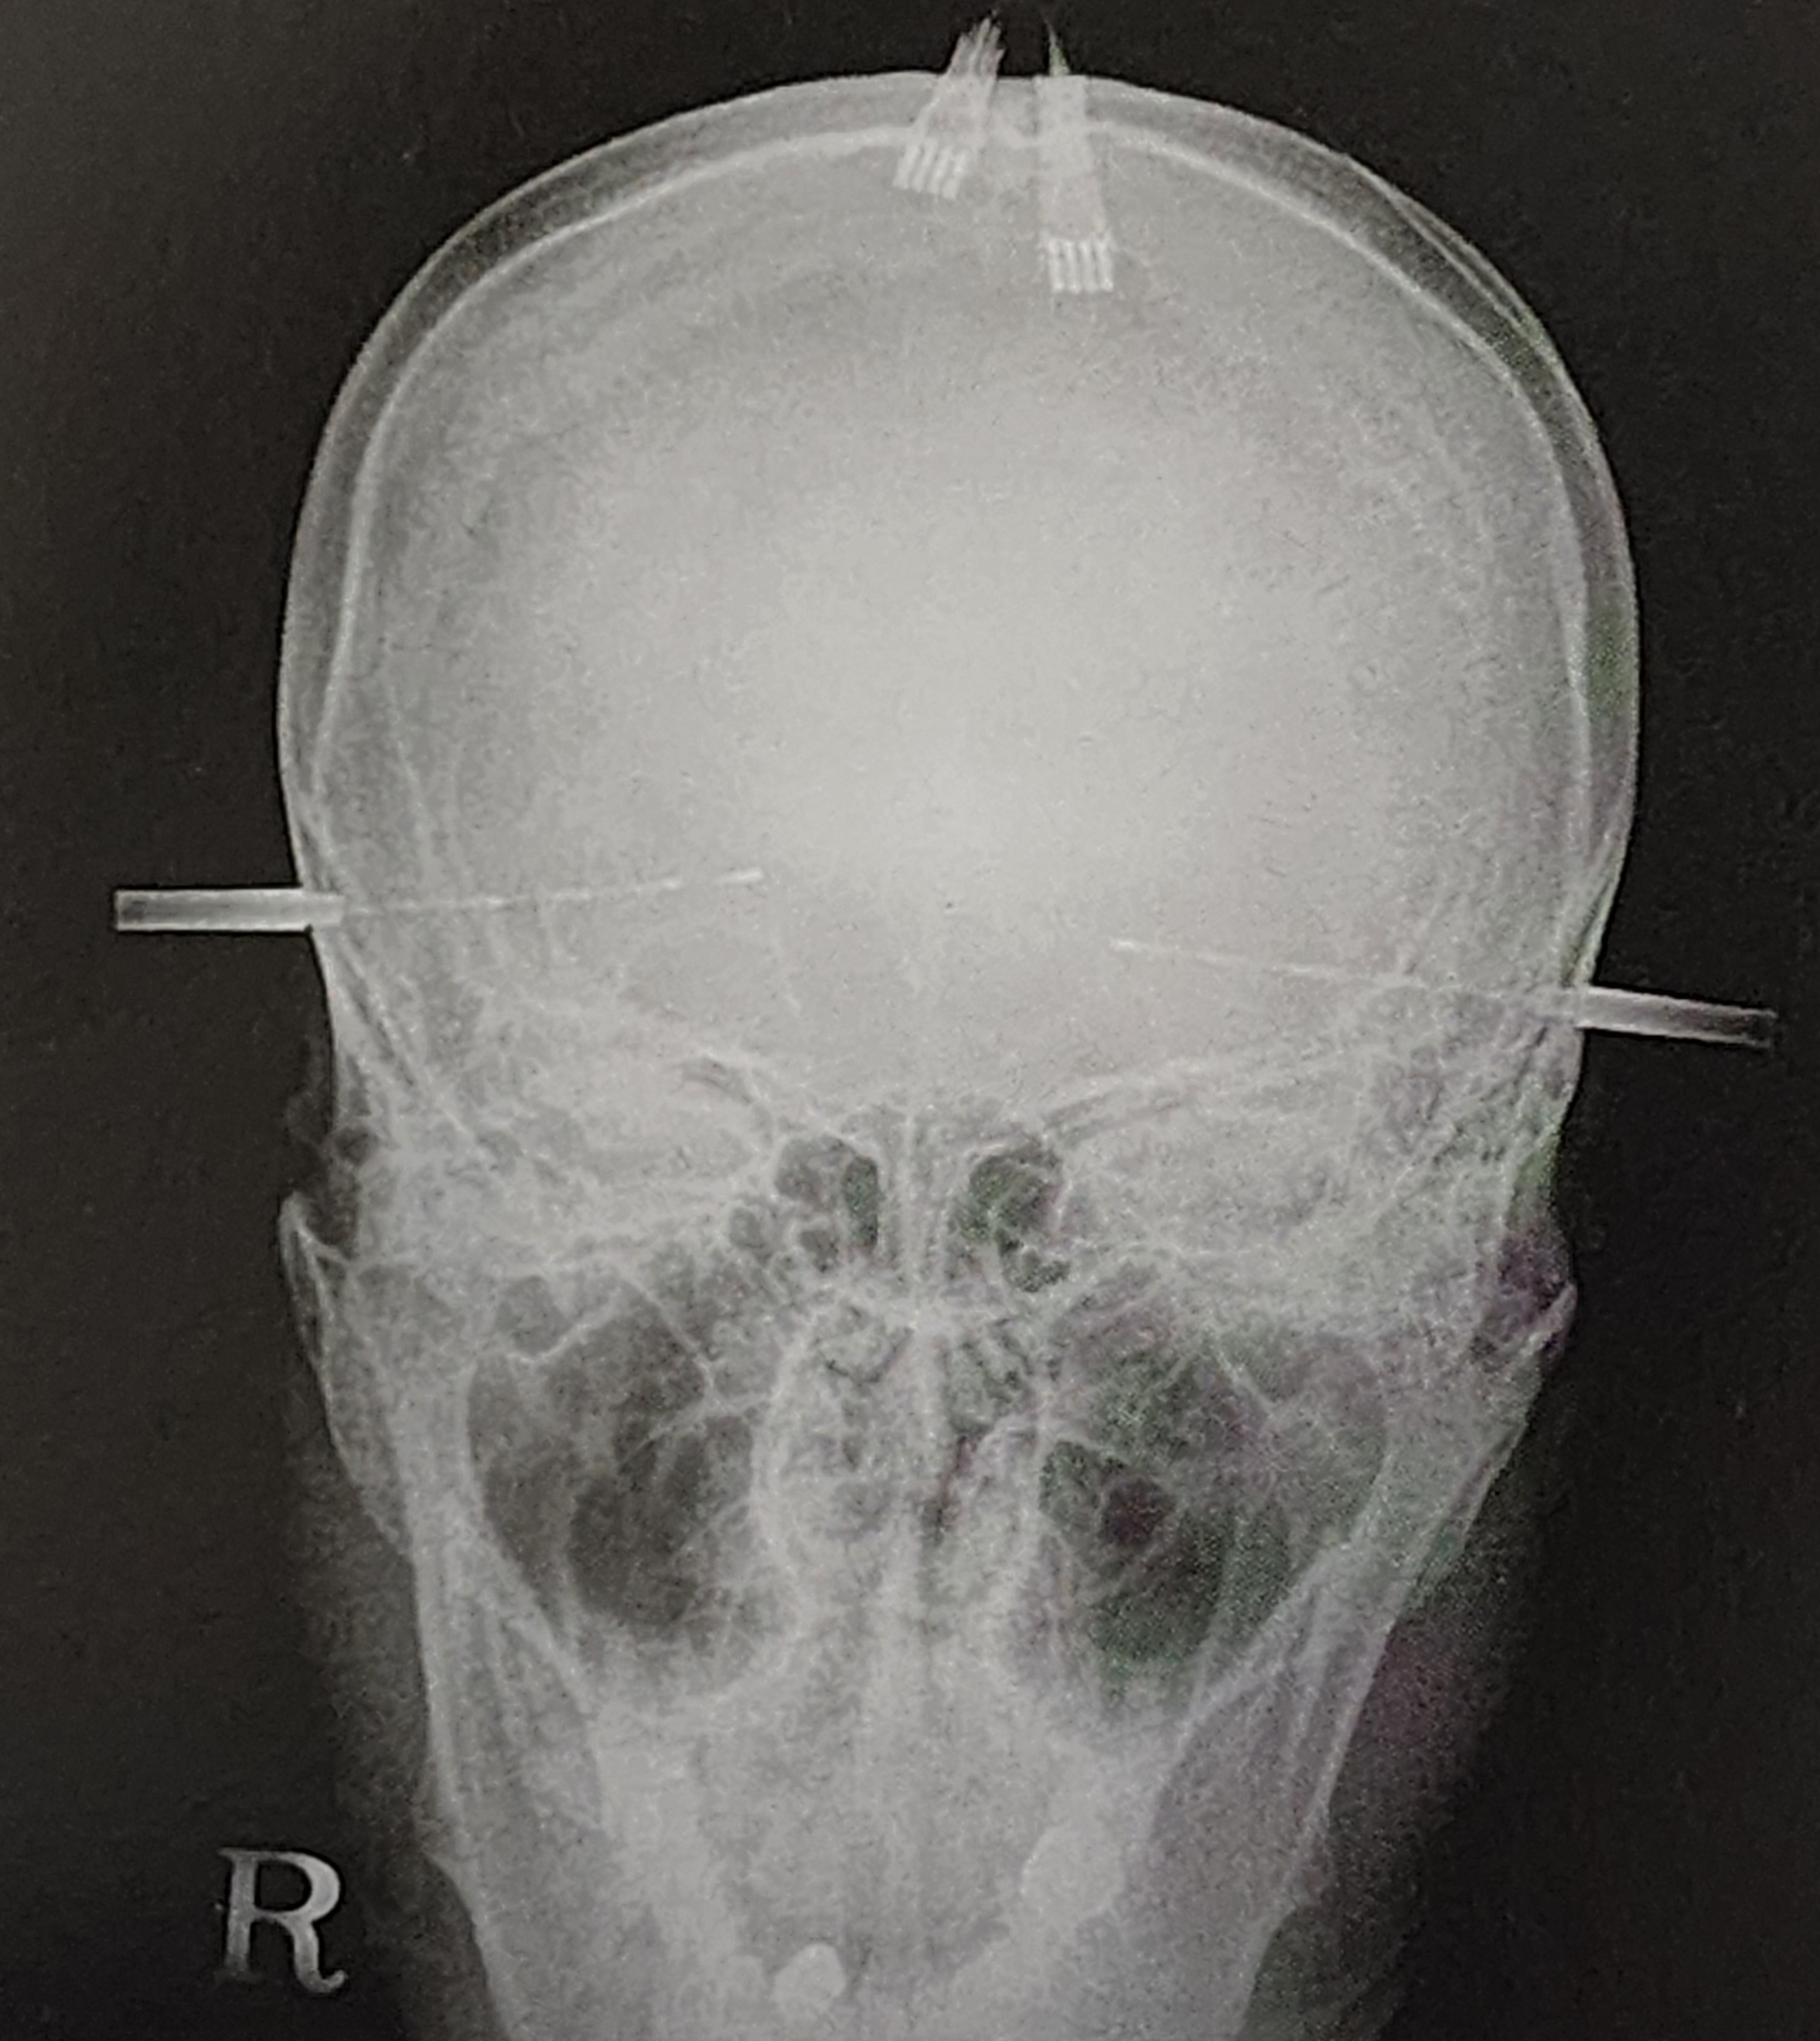

비침습적 검사만으로 발작의 정확한 위치를 결정하기 어려운 경우, 보다 정밀한 평가를 위해 침습적 검사가 필요하다. 침습적 검사는 전극을 두개골 내부에 삽입하여 직접 뇌파를 기록하는 방식이다.

(1) 심부전극(Depth Electrode) 검사

심부전극 검사는 뇌의 깊은 구조에서 뇌파를 기록하는 방법으로, 다음과 같은 경우 시행된다.

- 측두엽 간질이 의심될 때.

- MRI 검사에서 이상이 발견되지 않지만, 발작 부위를 보다 정밀하게 확인할 필요가 있을 때.

- 비침습적 검사 결과가 일치하지 않을 때.

심부전극 삽입 시 전극의 안정성과 감염 위험 관리가 중요하며, 삽입 후 일정 기간 동안 뇌파를 지속적으로 기록하여 발작이 어디에서 시작되는지 평가한다.

(2) 경막하 전극(Subdural Grid & Strip Electrodes) 검사

경막하 전극은 두개골 아래 경막에 직접 부착하여 넓은 영역에서 뇌파를 기록하는 방법이다.

- 전극이 그리드(grid) 형태로 배열될 경우 **경막하 격자 전극(subdural grid electrode)**이라 하며, 주로 피질 기능을 평가하고 병변의 범위를 정밀하게 결정하는 데 사용된다.

- 길게 배열된 형태는 **경막하 스트립 전극(subdural strip electrode)**이라 하며, 상대적으로 덜 침습적인 방법으로 특정 부위의 활동을 감시하는 데 유용하다.

경막하 전극 검사는 수술 후 운동 및 언어 기능을 보존할 수 있도록 발작 부위와 중요한 뇌 기능 부위의 거리를 평가하는 데 도움이 된다.